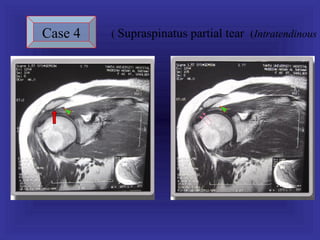

Case 4   ( Supraspinatus partial tear (Intratendinous